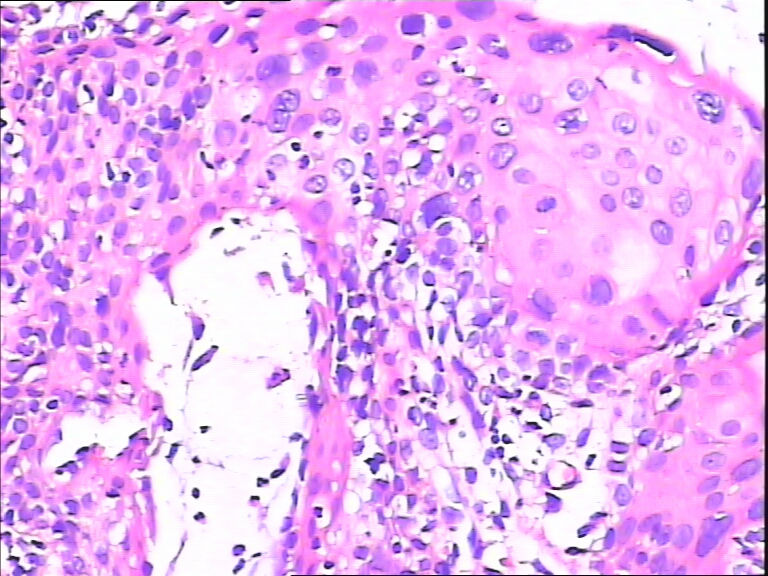

45y,触血,宫颈多点活检。